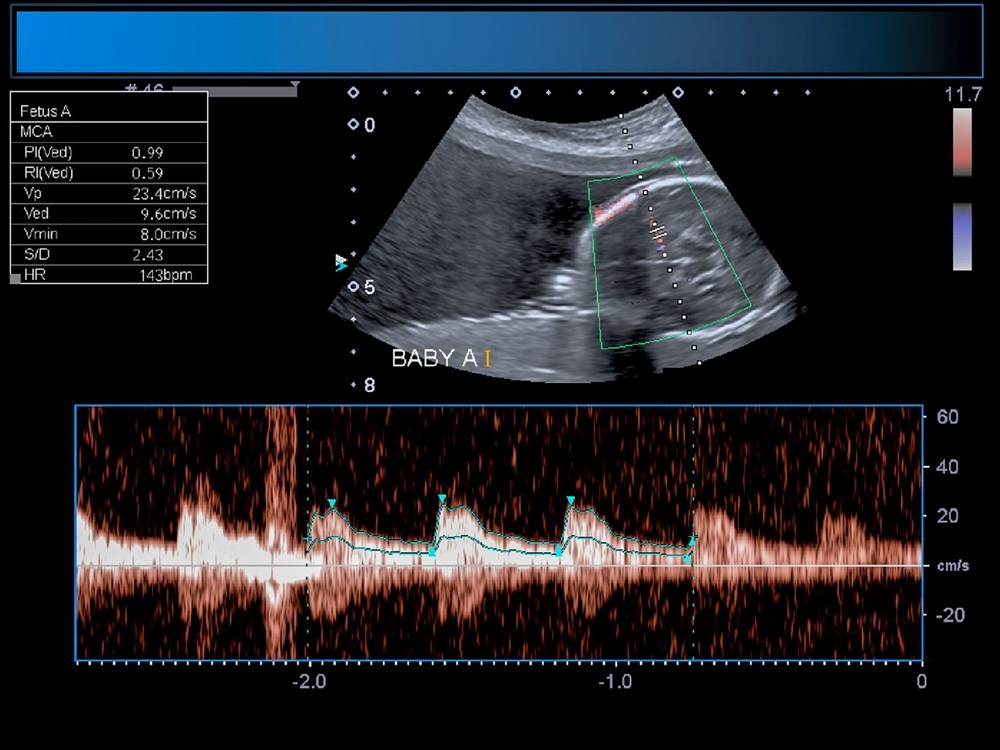

ABD'li doktorlar, türünün ilk örneği olan bir beyin ameliyatını çocuk henüz anne karnındayken gerçekleştirerek, doğmamış bir bebeği kesin ölümden kurtardı. Genetik bir bozukluk olan Galen damarı Malformasyonu'ndan (VOGM) muzdarip rahimdeki bebeğin kafatasını kesmeyi ve ardından gelişmekte olan beyni ameliyat etmeyi içeren titiz bir prosedür gerçekleştiren doktorlar, dünyada ilk kez yapılan operasyon ile birçok çocuğun hayatının kurtarılabileceğini müjdeledi.Türünün ilk örneği olan ve hayat kurtaran bir prosedürle anne karnındaki bir bebeğe beyin ameliyatı yapıldı.ABD'li doktorlar doğmamış çocuktaki ölümcül bir damar rahatsızlığını tedavi ederek doğumdan kısa bir süre sonra kalp yetmezliği ve felç geçirmesini önledi. Daha önce de rahimde beyin ameliyatı yapılmıştı, ancak Galen Damarı Malformasyonu (VOGM) adı verilen bu nadir hastalık için yapılmamıştı.Anneyi 34. haftada ameliyat eden bilim insanları, operasyonu yönlendirmek için ultrason kullandı. BEBEK SAĞLIKLI BİR ŞEKİLDE EVİNE DÖNDÜBoston Çocuk Hastanesi'nden Dr. Darren Orbach konuyla ilgili yaptığı açıklamada, "Genellikle doğumdan sonra görülen bebeğin sağlığındaki düşüşün ortaya çıkmadığını görmek bizi çok heyecanlandırdı. Şu anda altı haftalık olan bebeğin, ilaç kullanmadan, normal beslenerek ve kilo alarak eve döndüğünü bildirmekten memnuniyet duyuyoruz. Operasyonun beyin üzerinde herhangi bir olumsuz etki belirtisi yok." dedi. GALEN DAMAR FORMASYONU HAKKINDABununla birlikte, Galen Damar Malformasyonu (VOGM) her yıl yüzlerce bebeği etkiliyor ve çocuklar doğumun ilk birkaç gününden sonra hayatta kalamayabiliyor. Hastalık, beyindeki atardamarların kanı kılcal damarlar yerine doğrudan toplardamarlara akıtmasına neden olarak kalbin boğulmasına ve beyin hasarına yol açıyor.Mevcut tedaviler ise şimdiye kadar bebeğin doğumundan sonrası ile sınırlıydı, ancak bu noktada çoğu vakada beyin hasarı çoktan meydana gelmiş oluyordu. "Stroke" adlı bilimsel dergide sonuçları açıklanan yeni cerrahi operasyon, hastalığı bebeği etkilemeden önce iyileştirmeyi amaçlıyor.Diğer taraftan, operasyon kapsamında 10 sağlık görevlisinden oluşan bir ekip, annenin karnından uzun bir iğneyi bebeğin beyninin arterlerin etkilendiği kısmına yönlendirmek için ultrason kullandı. Doktorlar, daha sonra damarlara geri akışı engellemek için damar içine küçük bir madde enjekte etti.Dr. Orbach, "Bu yaklaşım, Galen Damarı Malformasyonu’nun tedavisinde büyük bir potansiyele sahip. Malformasyonu doğumdan önce onarıyoruz ve doğumdan sonra tersine çevirmeye çalışmak yerine kalp yetmezliğini ortaya çıkmadan önlüyoruz. Bu, bu bebekler arasında uzun vadeli beyin hasarı, sakatlık veya ölüm riskini önemli ölçüde azaltabilir." diye konuştu.